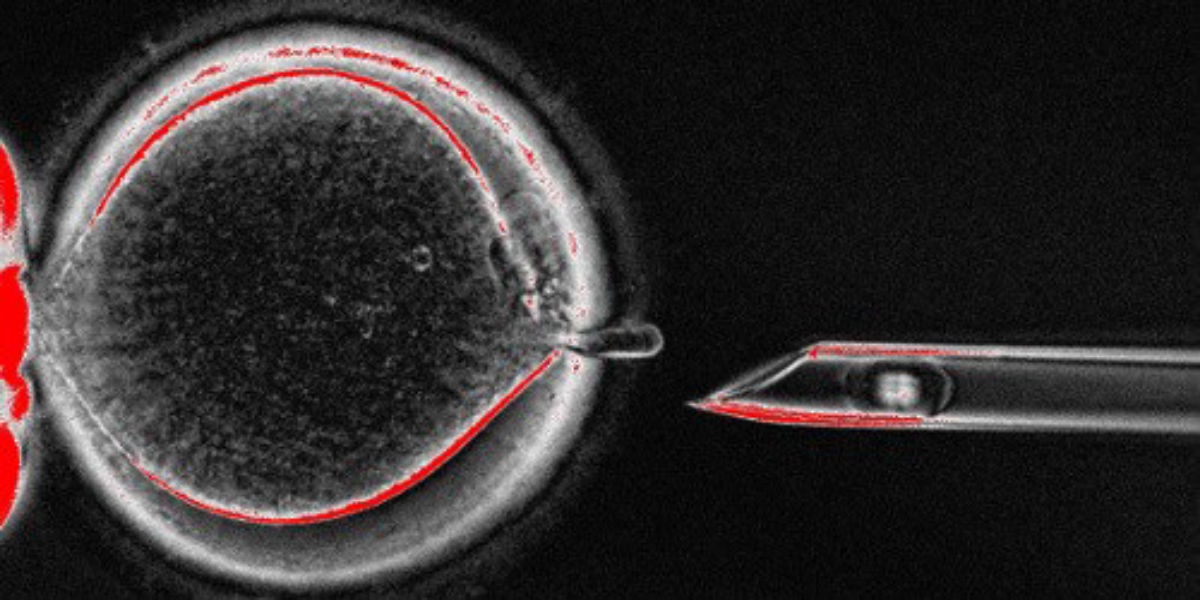

| MRT có thể giúp ngăn ngừa các bệnh di truyền do ADN ty thể. Ảnh: The Scientist Magazine. |